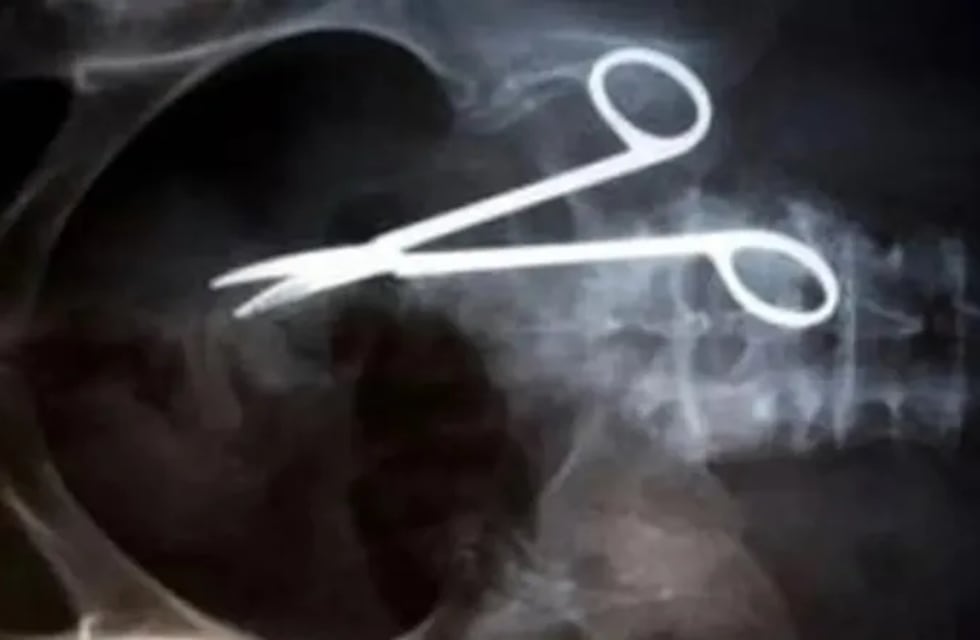

Los uniformados debieron trasladarlo a la enfermería y a través de las radiografías constataron que lo que decía era cierto. Los estudios médicos confirmaron que la tijera se encuentra alojada en el colon sigmoides, esto es a la altura de la pelvis. Mientras que la bombilla quedó en la zona del estómago. Hasta el momento no ha sufrido daños ni lesiones en los órganos vitales pero se estima que será intervenido quirúrgicamente.